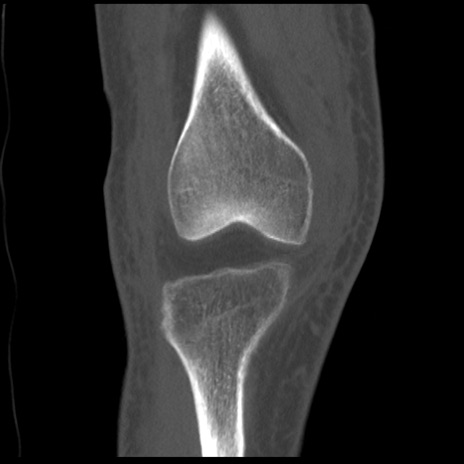

右膝関節CT

矢状断像